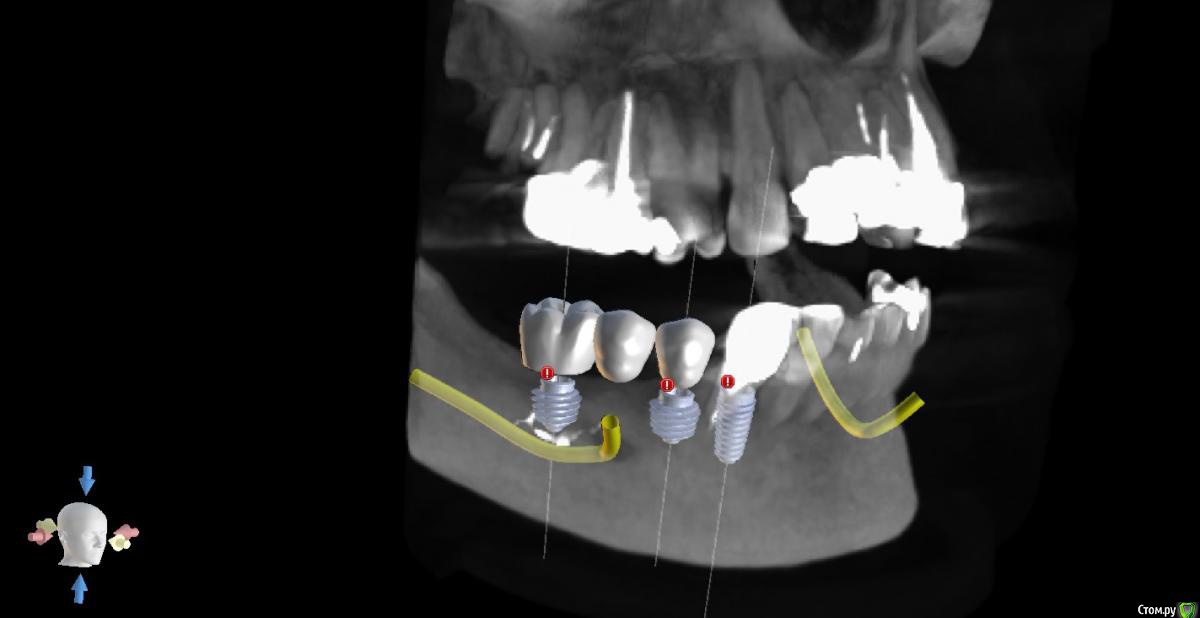

Премоляр под удаление и тоже имплантация. Ортопедические платформы будут находится на разном уровне...

А вот что в 4м квадранте...

В 4м квадранте очень красиво стают штрауман коротышки TL. Но в позиции 6го много пломбировочной массы (остатки). не хотелось бы с таким ценником расширять показания: ставить близко к нерву, делать мост и тем более делать высокие коронки.